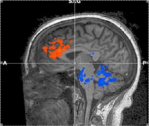

fMRI shows increased blood flow to frontal areas of brain and decreased blood flow in pons and cerebellum

fMRI images show significant areas of activation during Transcendental Meditation compared to resting with eyes closed. Areas of activation (orange) included the anterior cingulate gyrus and the dorsolateral prefrontal cortex. Areas of deactivation (blue) included the pons and cerebellum. These findings suggest the mind is alert but that mind and body are in a deeply restful state.

Functional magnetic resonance imagining (fMRI) patterns of 16 subjects during their practice of Transcendental Meditation found that, like meditations that involve focused attention or open monitoring, there was increased activity in the areas of the prefrontal cortex related to attention – indicating alertness. However, unlike other meditations, during Transcendental Meditation there was also decreased activity in the areas related to arousal – indicating deep rest.

Compared to just resting peacefully with their eyes closed, the fMRI scan found an increase in blood flow in the bilateral anterior cingulate gyrus and bilateral dorsolateral prefrontal cortices – areas of the brain’s prefrontal cortex associated with attention and executive functions such as decision making, reasoning, working memory, inhibition, and reward anticipation.

Frontal blood flow is also reported during other meditations and indicates that the mind is alert.

However, unlike other meditations, during Transcendental Meditation there was a decrease in blood flow to the pons and cerebellum. The pons modulates the individual’s overall state of arousal and governs breath and heart rates. The decrease in activity in this brain area supports the experience during Transcendental Meditation of a deeply silent mind and rested body.

The cerebellum modulates the speed and variability of information processing, both related to coordination and motor control and to cognitive functions such as attention and language. The decrease in activity suggests that the body reverts to a more automatic mode without the need of cognitive effort to exert control.

Together the decrease in activity in the pons and cerebellum activity suggests an overall reduction in cognitive control and executive processing during Transcendental Meditation – as if the attentional system is at a balance point ready to act when needed, Dr. Travis said.